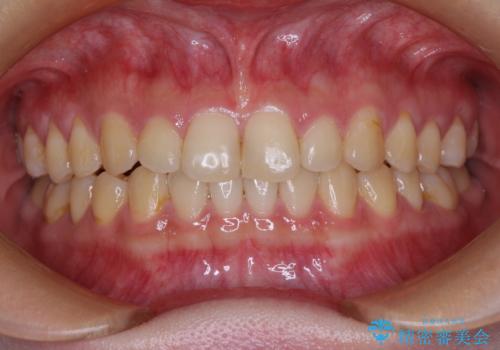

治療途中の奥歯と矯正治療の後戻り インビザライン・ライトによる矯正治療

- 20代女性

- インビザライン・ライト

- 根管治療を行ったままの奥歯と、矯正治療の後戻りを気にして来院された患者様です。

根管治療された歯に症状はなく、オールセラミッククラウンにて補綴治療を行うこととしました。

矯正治療の後戻りは軽微であったため、インビザラインの簡易パッケージであるインビザライン・ライトを用いて歯列を整えることとしました。

クラウンはよりよい咬み合わせで装着したいため、インビザラインを1セット使用して概ね歯列を整えた時点で補綴治療を行い、その後仕上げの矯正治療を行いました。